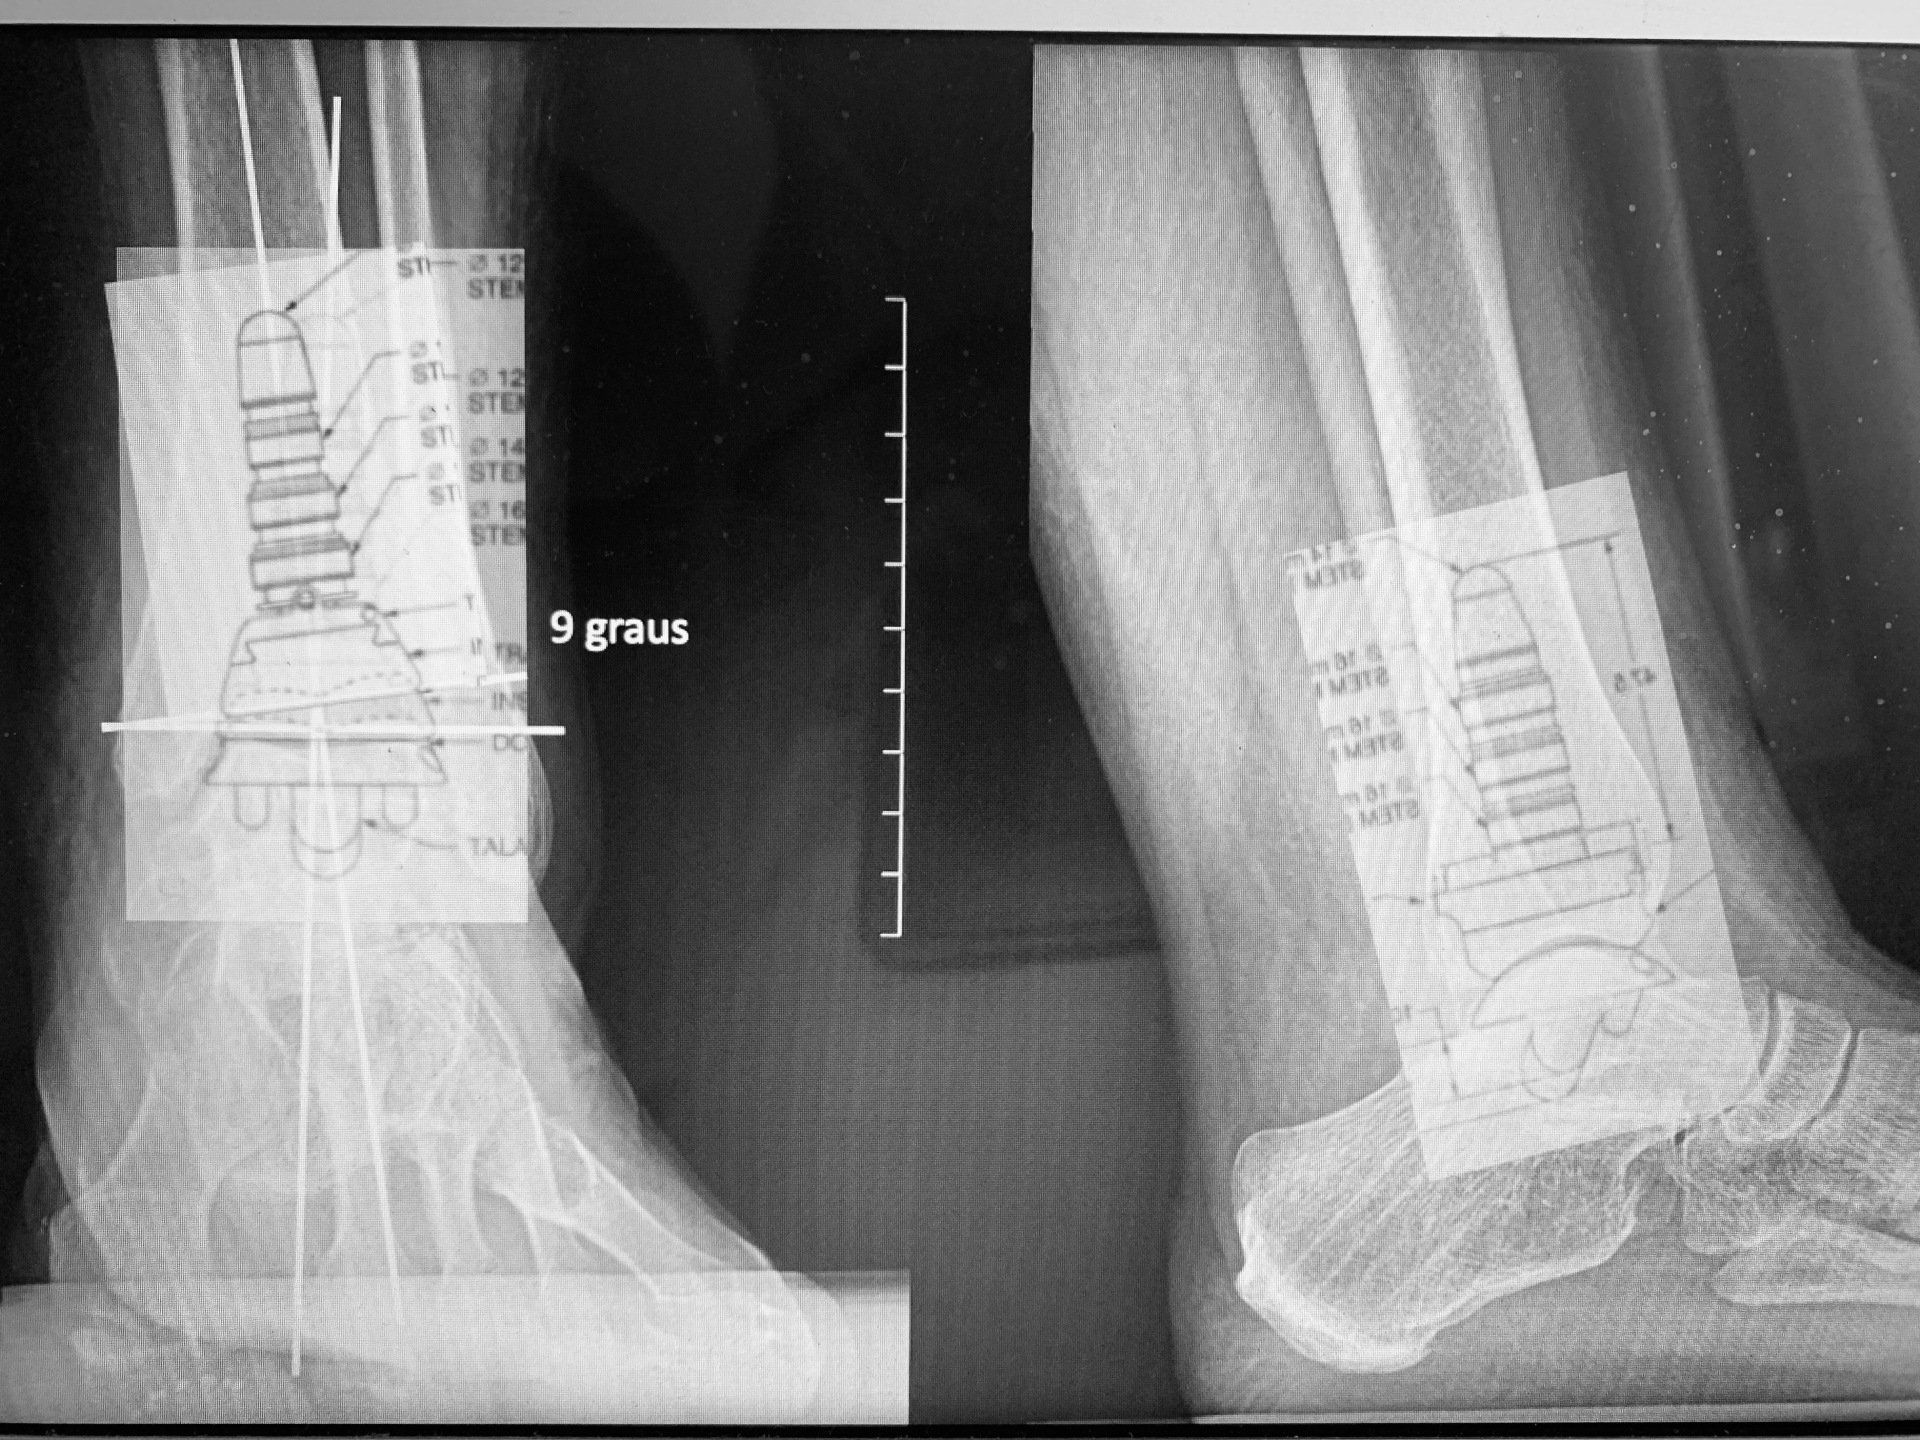

05/12/2020: As fraturas do tornozelo podem levar a um processo degenerativo chamado de artrose ou osteoartrose. O estágio final desta doença se caracteriza por dor e limitação da marcha. Uma das soluções de tratamento é a Artroplastia Total do Tornozelo ou prótese de tornozelo, que tem o objetivo de eliminar a dor e devolver a função. Este sábado podemos realizar mais uma prótese de tornozelo para tratamento de um quadro de osteoartrose pós-traumática.

Parágrafo Novo

Paciente do Paraguai foi submetido a Artroplastia Total do Tornozelo neste último sábado no Hospital Viver de Ribeirão Preto com o Dr Rogério Bitar e o Dr Alexandre Leme Godoy dos Santos. O paciente optou pela artroplastia após ter passado por diversos médicos que sugeriram fazer a fusão do tornozelo. O paciente segue em recuperação.